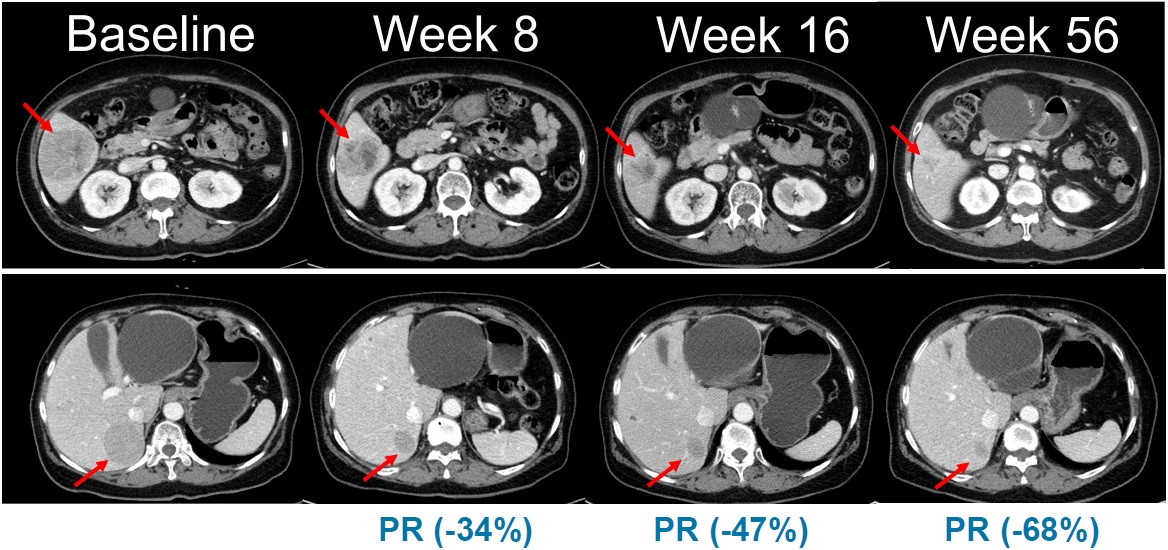

Abdominal CT images showing changes in tumor lesions over time in a clinical trial of combination therapy with belvarafenib and cobimetinib in patients with NRAS-mutant melanoma. (Source: Oral presentation at the American Society of Clinical Oncology [ASCO] Annual Meeting, 2021)

Abdominal CT images showing changes in tumor lesions over time in a clinical trial of combination therapy with belvarafenib and cobimetinib in patients with NRAS-mutant melanoma. (Source: Oral presentation at the American Society of Clinical Oncology Annual Meeting, 2021)